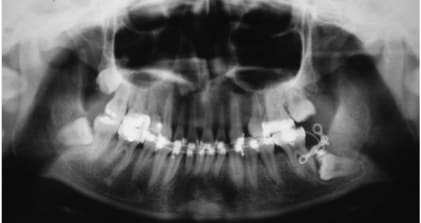

Verdict des prof, redresser cette dent est parfaitement faisable mais :

- surement plus d'un ans de traitement

- risque de résorption radiculaire laissant la dents avec un rapport couronne racine défavorable sur le long terme

Eux ils peuvent faire mais ça ne leur semble pas la meilleur option pour le patient, si il avait était plus jeune ça se serait discuté.

Ensuite en discuté avec le patient, j'avais vue un cas réalisé par un généraliste japonais ou il avait distalisé une 45 avec une minivisse pour pouvoir faire un bridge.

Pourquoi un bridge et pas un implant ? très simple le patient ne voulait pas d'implant (la minivisse par contre pas de problème)

Si joint de illustration tiré de publication, juste pour montrer a notre amis alapex que si pour une raison X ou Y ont veut récupérer cette 8 c'est faisable, compliqué cher mais faisable.